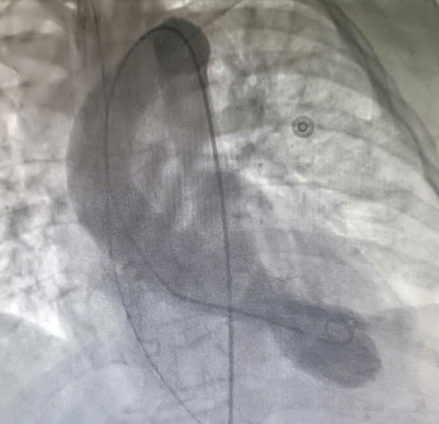

| Trước: Hình chụp tâm thất trái cuối tâm thu. Sau: Cuối tâm trương – giảm động vùng mỏm và tăng co bóp ở vùng đáy - Ảnh BVCC |

Mặc dù chụp mạch vành không phát hiện tổn thương tắc nghẽn, các bác sĩ tiếp tục quyết định chụp hình ảnh buồng tim. Kết quả cho thấy rối loạn vận động điển hình của hội chứng Takotsubo, với tăng co bóp ở đáy và giảm vận động ở mỏm tim, xác định đây là bệnh cơ tim cấp do căng thẳng.